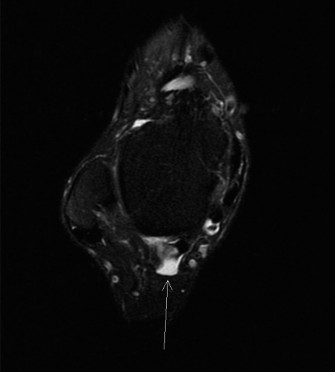

التصوير بالرنين المغناطيسي (MRI)

-

ماذا يظهر:

يُعد الرنين المغناطيسي هو الفحص الذهبي لتقييم الأنسجة الرخوة مثل الأوتار والأربطة والغضاريف. في حالة التهاب وتر قابضة إبهام القدم الطويلة، يُظهر الرنين المغناطيسي:

- التهاب الغمد الوتري: تراكم السوائل والتورم حول وتر قابضة إبهام القدم الطويلة.

- اعتلال الوتر: تغيرات في نسيج الوتر نفسه، مما يشير إلى التهاب مزمن أو تآكل.

- تضيق النفق: ضيق في النفق الليفي العظمي الذي يمر من خلاله الوتر، مما يؤدي إلى انضغاطه.

- العظم المثلث: يُظهر العظم المثلث بوضوح، مع أي تورم أو التهاب في الأنسجة المحيطة به، مما يؤكد مساهمته في الانحشار.

- استبعاد إصابات أخرى: يساعد الرنين المغناطيسي في استبعاد مشاكل أخرى مثل اعتلال وتر أخيل، أو التهاب وتر الظنبوب الخلفي، أو إصابات الأربطة.

- أهميته: يوفر الرنين المغناطيسي تفاصيل دقيقة حول مدى التهاب الوتر، وجود العظم المثلث، وتأثيره على الهياكل المجاورة، وهو أمر حاسم لتخطيط العلاج، خاصةً إذا كانت الجراحة ضرورية.

الشكل 1: صورة رنين مغناطيسي محوري لوتر قابضة إبهام القدم الطويلة ضمن نفقها الليفي العظمي. لاحظ القرب الشديد للحزمة الوعائية العصبية الظنبوبية الخلفية (إنسي لوتر FHL). توضح هذه الصورة النتائج النموذجية في أمراض وتر FHL، حيث يظهر الوتر (غالبًا مع زيادة الإشارة أو السائل المحيط به) مقيدًا بنفقه التشريحي.